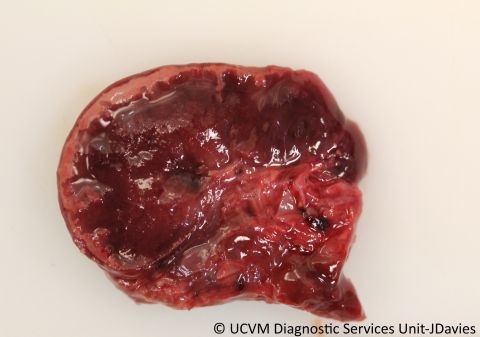

Species: Ruminant, Bovine

Mesenteric lymph node

Necrotizing lymphadenitis caused by Salmonella typhimurium